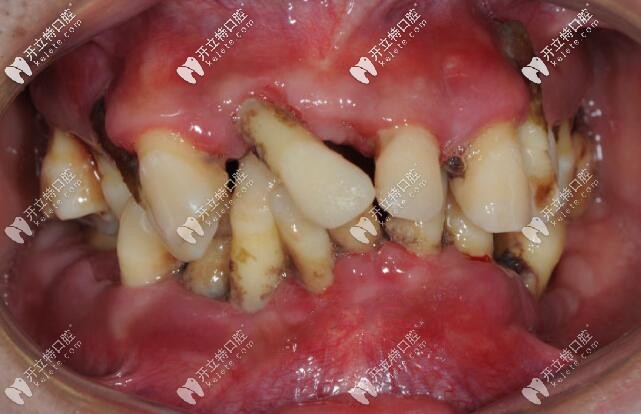

案例二、35歲大叔,全口牙槽骨重度吸收,全部牙齒都漂浮在骨頭之上,后來(lái)也是拔掉了全部牙齒,做了活動(dòng)義齒。

35歲重度牙周炎顧客的牙齒情況

據(jù)這位大叔叔自述,他曾經(jīng)也因?yàn)檠腊蔚羧谘篮蠓N牙費(fèi)用太高,一度選擇不治。

重度牙周炎顧客的牙齒不治療可以嗎

不過(guò)一年后他還是再次走進(jìn)了醫(yī)院,接受了拔牙+全口活動(dòng)義齒的治療方案。